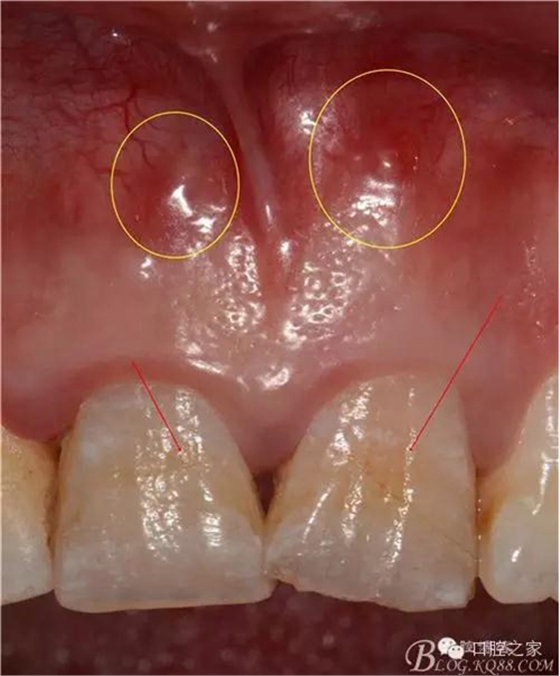

根管內(nèi)因素治療失敗,查清原因后重新治療,大都可以治愈。根管外因素所致失敗,除部分病例配合外科可以治愈,大多數(shù)病例重新作根管治療也難以成功,形成真正的難治性根尖周炎。筆者在《實(shí)用牙髓病診療學(xué)》中將竇道口形狀分為6種,其中的膿性針眼狀竇口(壓有白色膿液溢出,竇口僅有針眼大小無(wú)突起)幾乎都是根管外原因,單純根管治療難以奏效。